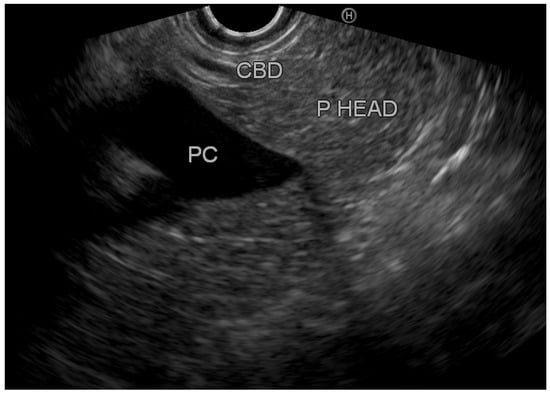

Overall, we identified eight patients with inflamed tissue on EUS (group A) vs. 42 patients with normal pancreatic tissue (group B). Figure 2 demonstrates an EUS image with inflamed pancreatic head tissue (heterogeneous echo pattern, decreased echogenicity with edema), and Figure 3 demonstrates normal pancreatic head parenchyma. All patients in group A had clinically mild acute pancreatitis. However, in group B, 33 patients (78.6%) had mild disease, 7 patients (16.7%) had moderate disease, and 2 patients (4.8%) had severe disease. Exploring the optimal timing for performing EUS, we found that among patients with normal pancreatic tissue, the average period until performing EUS from hospital discharge was 44.7 ± 28.3 days (20–120); among patients with inflamed pancreatic tissue, EUS was performed 48.1 ± 22.3 days (20–90) from discharge. Table 2 demonstrates the characteristics of patients with inflamed and normal pancreatic tissue on EUS.

Figure 2. Inflamed pancreatic parenchyma. P HEAD: pancreatic head.

Figure 3. Normal pancreatic parenchyma. CBD: common bile duct; PC: portal confluence; P HEAD: pancreatic head.